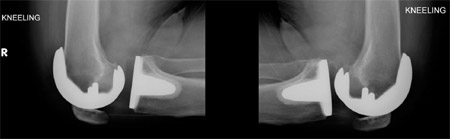

Radiographs of the knees of one male patient were made three months after bilateral total knee arthroplasty to evaluate kneeling (Fig. 5).

fig 5

Fig. 5 Radiographs of the knees of a male patient, made with the patient kneeling on a thick pad three months after bilateral total knee arthroplasty.

Pain with kneeling may also be attributed to factors other than the incision. If there is flexion instability with posterior subluxation, kneeling may cause pain as the tibia is forced posteriorly and the femur moves anteriorly. This was unlikely in our patients because of the congruency of the components and the substantial lip of the tibial component (Fig. 5). Pain may also be caused by the host patella flexing over the component. This happens if the resection has been too aggressive, leaving a thin, flexible host patella.